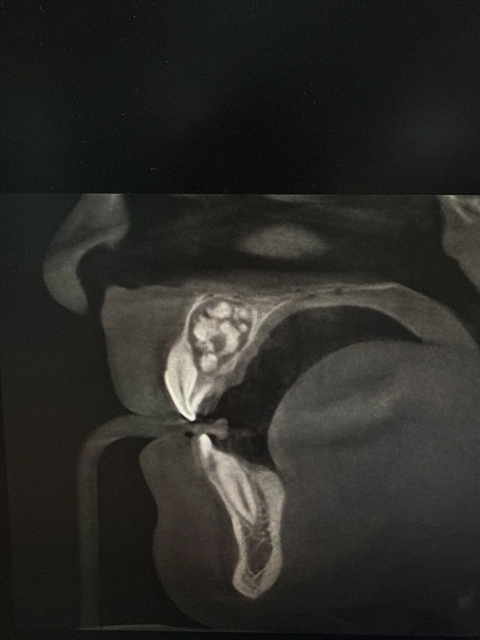

完善相关辅查后,科室医生李颂通过微创手术的精细操作,成功将这一堆“小牙齿”全部取出来!

被取出的“牙瘤”